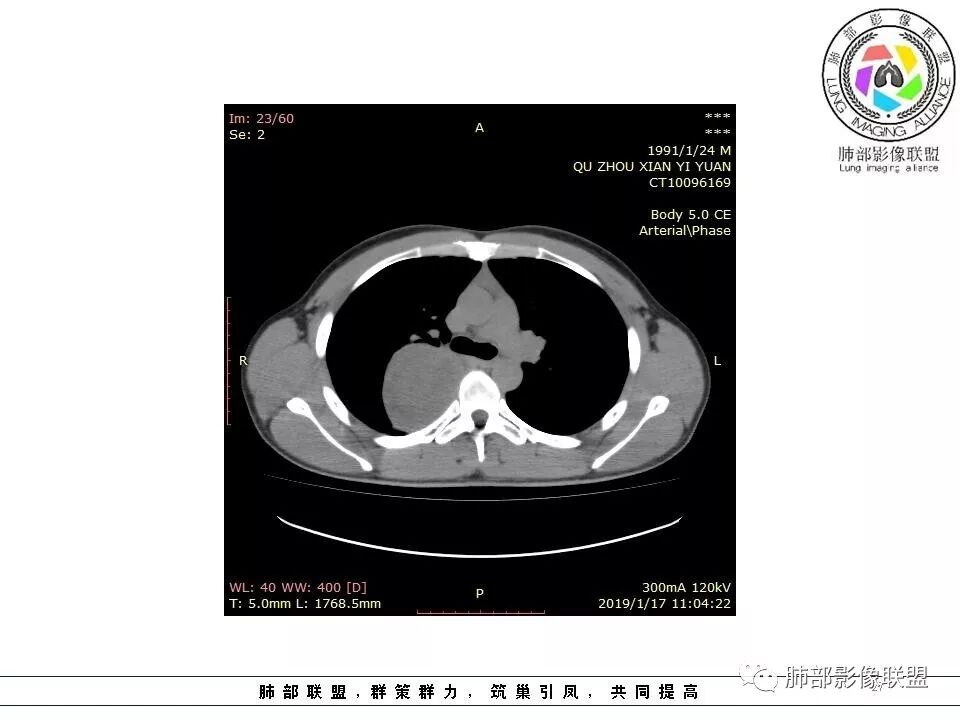

后纵隔脊柱旁占位性病变,有胸膜尾征,胸膜下脂肪可见,蛇纹征,明显强化。考虑孤立性纤维瘤。

病灶定位脏层胸膜,肺组织受挤压,有胸膜尾征,动脉期可见血管支配,考虑肺动脉供血,静脉期,强化增强明显,符合快进慢出特点,病灶内可见低密度区,考虑胸膜孤立纤维瘤。

右侧后纵隔脊柱旁占位,边缘光滑清晰,内侧肺组织受压,外侧可见胸膜尾征,增强持续强化,并可见蛇纹血管征。考虑SFT

后纵隔脊柱旁占位性病变,有胸膜尾征,胸腔积液外推,蛇纹征,考虑孤立性纤维瘤。

右侧后纵膈肿块,有胸膜尾征,周围肺组织及支气管被推压,定位肺外,脏层胸膜来源,血供来自肺动脉或者支气管动脉,增强后持续渐进强化,蛇纹征,考虑SFT,鉴别鞘瘤。

右后纵膈肿块,肺瘤界面清楚,胸膜尾征,邻近肺组织及支气管被推移,部分脂肪间隙存在,定位肺外来源,血供来自肋间动脉,增强后持续渐进强化,蛇纹征,考虑SFT,鞘瘤肿块内血管罕见,不考虑。

右上肺野脊柱旁软组织肿块,边缘光滑整齐,肺组织及气管右肺上叶支气管受压前移,外移,边缘可见胸膜尾征,病灶内密度不均,增强后渐进性持续强化,其内可见明显蛇纹血管征,首先考虑肺外来源,sft.可能性大

青年男性,右侧脊柱旁占位,瘤肺界限清晰,支气管推移,胸膜尾,D字征,胸膜下脂肪影,蛇纹血管,双重供血,延迟强化,定位胸膜,支持sft

青年男性,瘤肺边界锐利,气管向前推移,定位肺外,局部胸膜增厚,后方见少量积液,提示脏层胸膜来源,增强持续渐渐进性强化,内见蛇纹血管,考虑sft

脏层胸膜主要由支气管动脉和肺动脉供血,壁层胸膜主要由支气管动脉,胸廓内动脉、肋间动脉供血

如果是肋间动脉,就不可能是脏层胸膜,可以是壁层或者纵膈

但是这个病人,肋间动脉供血吧,我倾向胸膜

供血,体外供血,体循环,要么是壁层胸膜,要么胸膜外的,脏层胸膜应该是对内供血。病变里面的血管,除非是非常粗大迂曲的血管,不然,我不认为是其特点。

脏层胸膜肺内供血,壁层胸膜体外供血